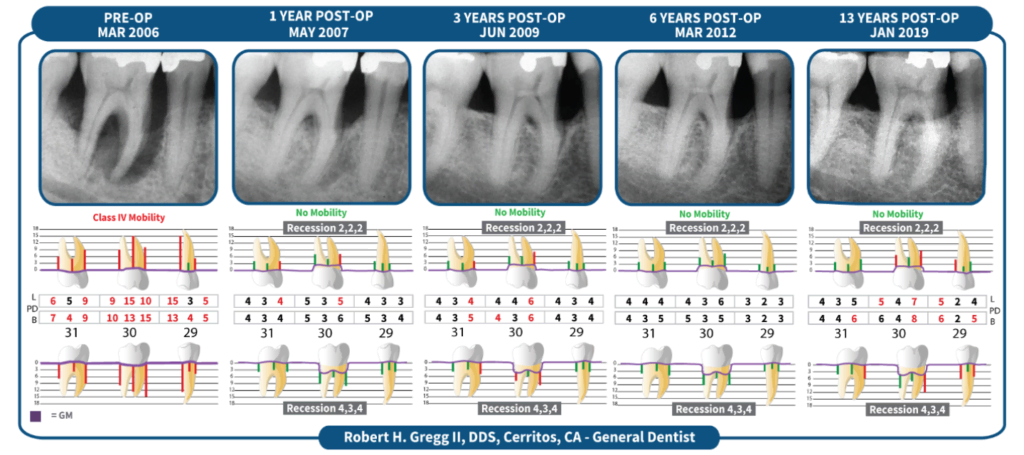

The LANAP® Protocol is a comprehensive approach to treating moderate to severe periodontal disease by delivering true regeneration of the attachment apparatus including new cementum, periodontal ligament, and bone on a previously disease root surface. 510(k) K151763

Tooth survival over time – a measurement of LANAP® success

Webinar presented by Lloyd Tilt, DDS, MS

One of the key criteria for determining the success of periodontal therapies is tooth survival over time – a critical factor when discussing treatment recommendations with patients. The second periodontist to adopt the LANAP® Protocol, Dr. Tilt reviews the retrospective data of his treatment results published in General Dentistry. 1 CEU